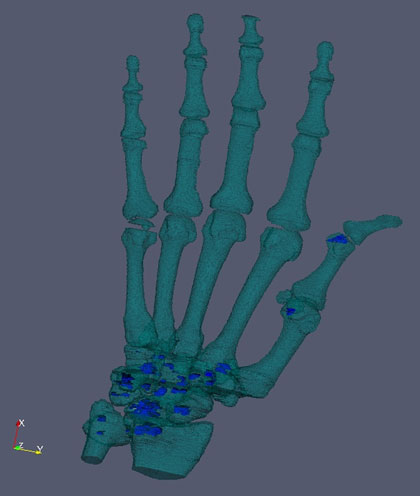

Additionally we are pursuing several different but related research projects. Methods have been developed and validated to characterize progression the progression of hip and hand OA radiographically (5). In collaboration with Dr. Chris Evans at the Mayo Clinic, Dr. Duryea was recently awarded a supplemental grant to support a study testing the hypothesis that a novel method based on conventional radiography can be used to detect the status of osseous defects with high accuracy. We have also received a NIH grant to support a study to evaluate hand radiography in conjunction with a study of adiposity-related metabolic factors as predictors of incident hand OA. In collaboration with Daniel Solomon in the BWH Rheumatology Division, Department of Medicine we are developing methods to assess hand RA using multi-slice CT. With Drs. Anthony Aliprantis and Matthew Harris, we have initiated a project to apply quantitative methods to assess bone parameters of zebra fish.

Hand CT to evaluate RA erosions |